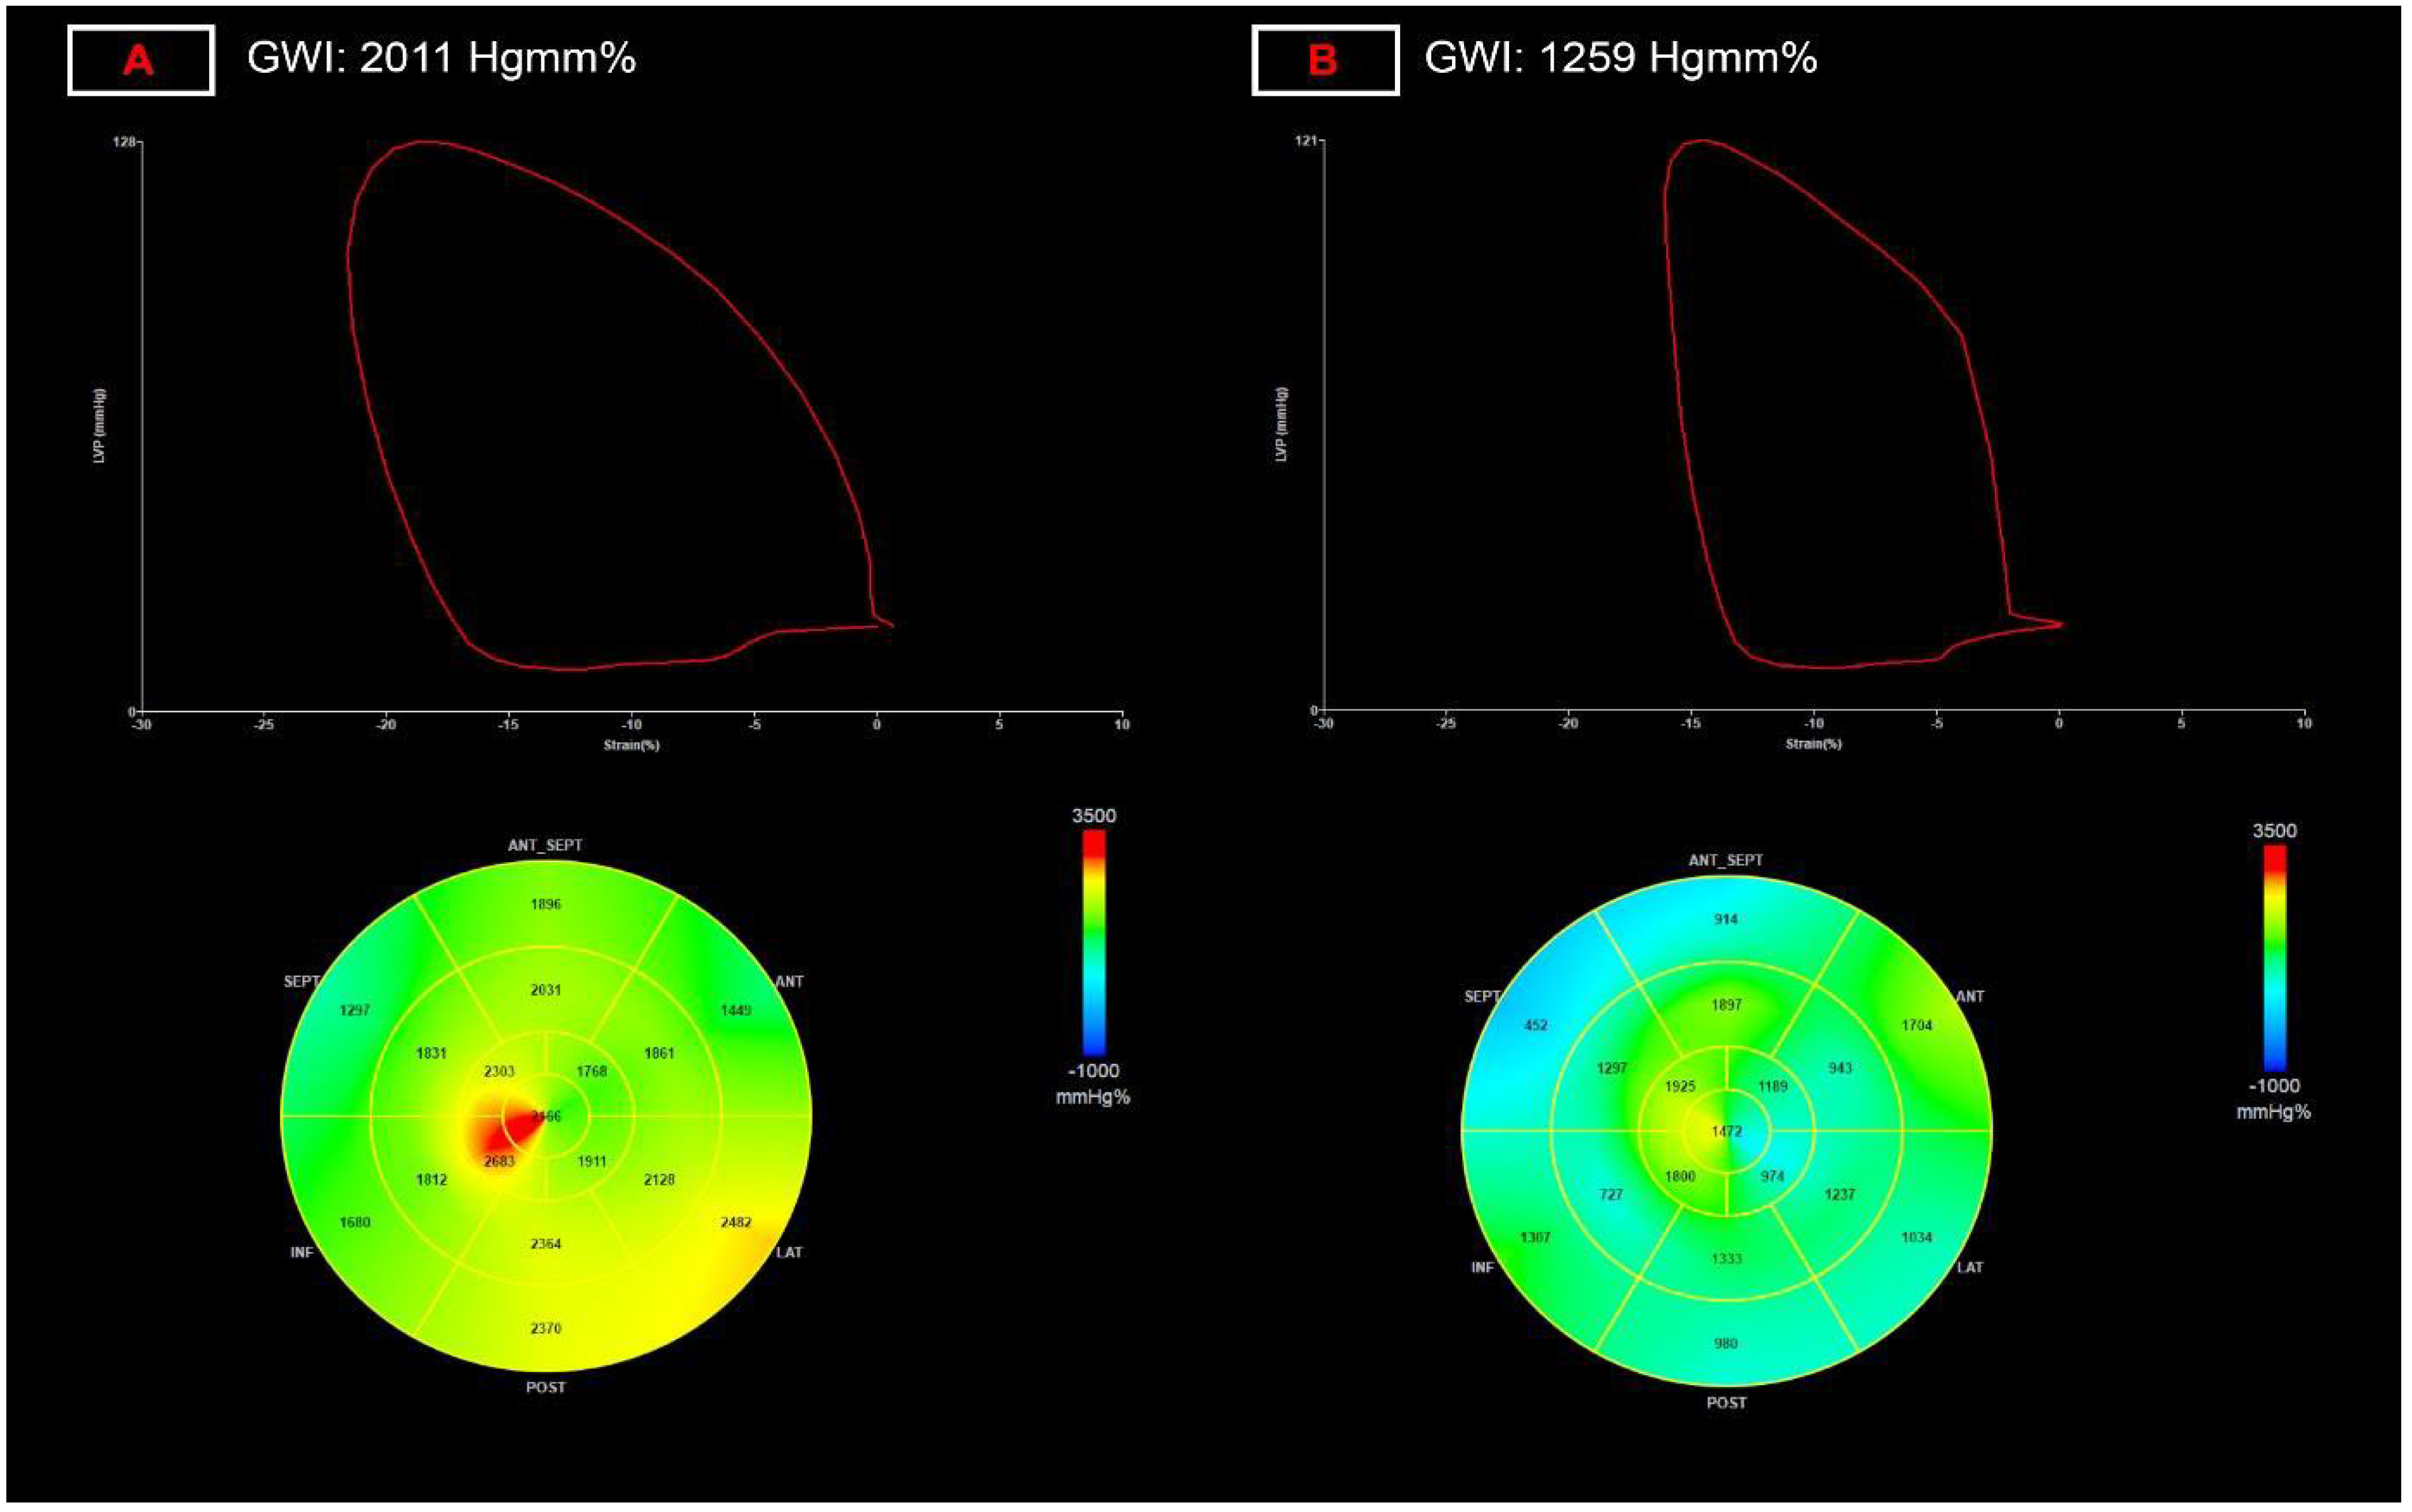

3.3. Myocardial Work Parameters

- Along with non-invasive measurement of stroke volume, deformation imaging appears to be able to detect the most pronounced relative difference for both left and right ventricular function, with left ventricular global myocardial work index and right ventricular free wall strain being the most robust alteration;

- These minor changes are difficult to utilize on a single patient basis, however, LV myocardial work and RV free wall strain seem to be the most sensitive and reproducible 2D echo-based functional parameters for screening for cardiac injury and follow-up;

| LV global work index, Hgmm% | 1975 (1789–2105) | 1829 (1656–2057) ** | 7.4 |

| LV global constructive work, Hgmm% | 2383 (2226–2577) | 2341 (2094–2559) | NA |

| LV global wasted work, Hgmm% | 99 (63–129) | 107 (77–151) | NA |

| LV global work efficiency, % | 96 (94–97) | 95 (93–96) * | 1.0 |